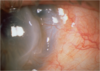

Herpes Zoster opthalmicus